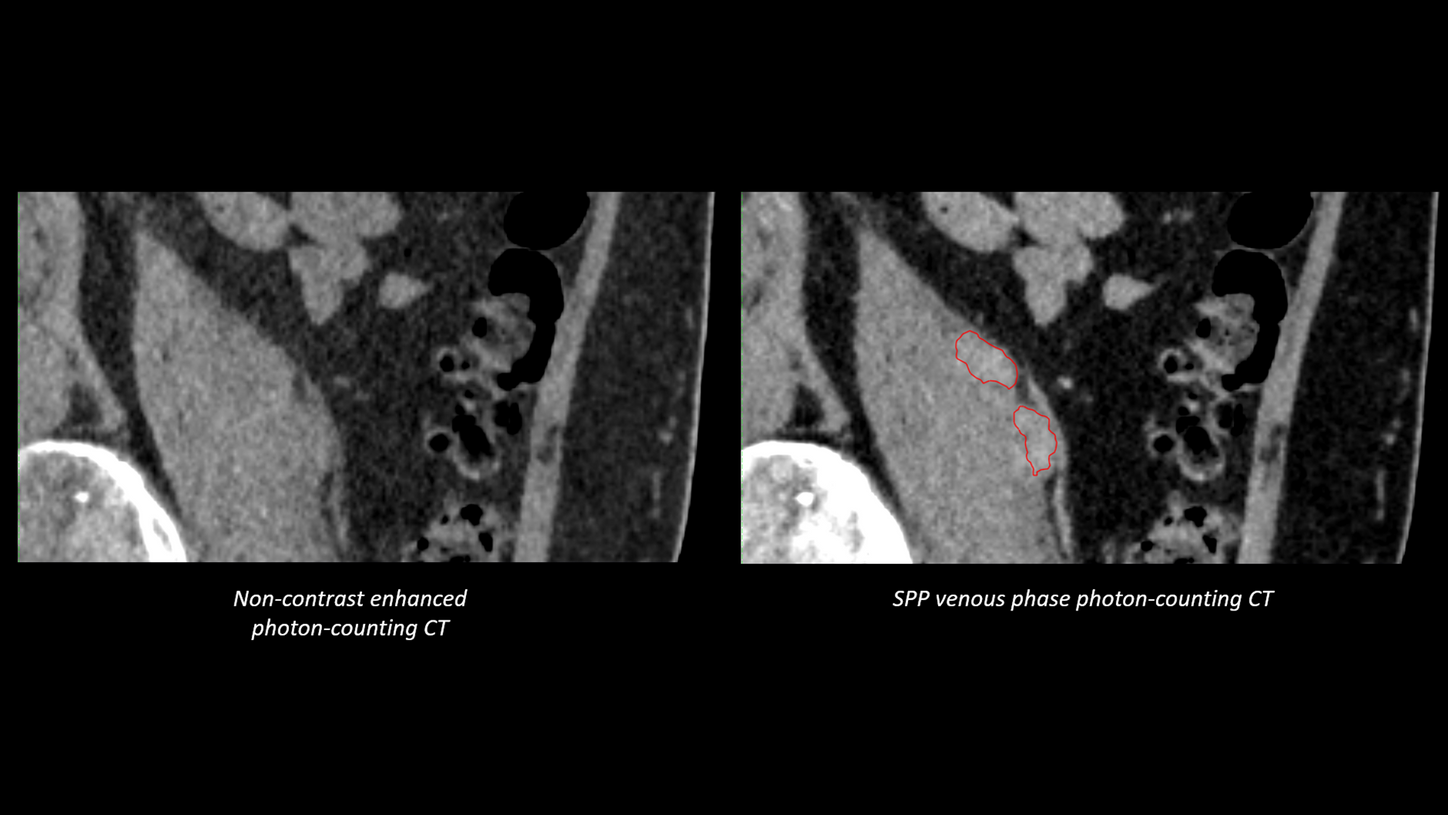

"Compared to previous images, those acquired with our new photon-counting scanner show considerably greater detail. For instance, we can now detect very small liver lesions as small as 4 mm on post-contrast images. The enhanced visibility provided by photon-counting technology enables us to use much narrower margins between the GTV and CTV, allowing for dose escalation鈥攎ight lead to improved patient outcomes." 9